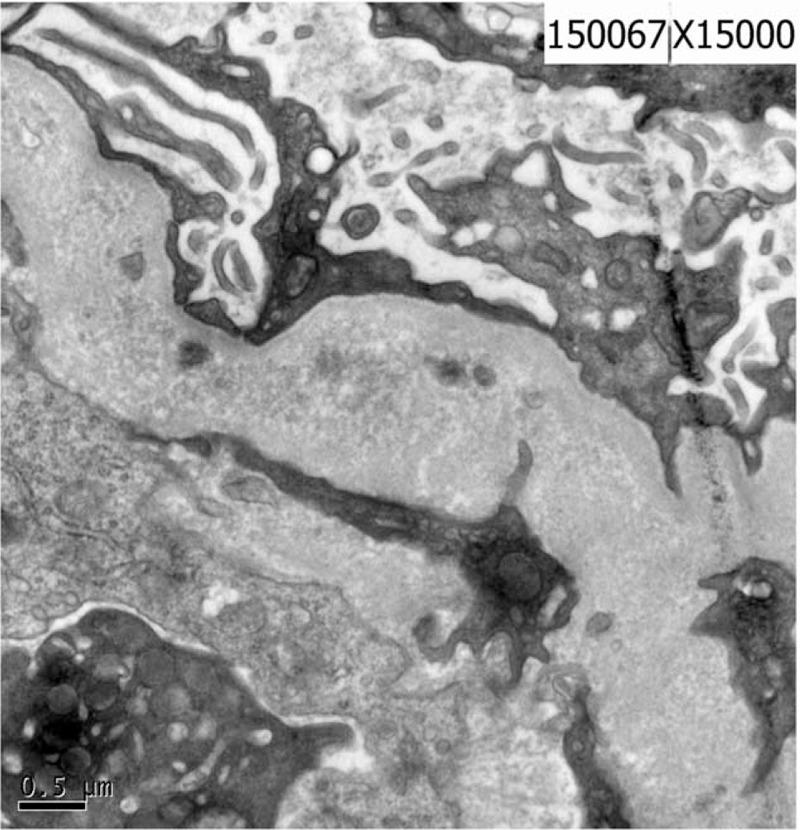

Based on severe normochromic anemia and acute kidney injury, renal biopsy showed membranous proliferative glomerular lesions and thrombotic microvascular disease, supporting the diagnosis of aHUS. Although the serum vitamin B12 was normal, further investigation found the concentration of urinary methylmalonic acid and serum homocysteine increased obviously, genetic analysis revealed a heterozygous MMACHC mutation (exonl: c. 80A >G, c. 609G >A). The final diagnosis was aHUS induced by inherited methylmalonic acidemia (MMACHC heterozygous mutation exonl: c. 80A >G, c. 609G >A).

基于重度正细胞正色素性贫血及急性肾损伤,肾活检显示膜增生性肾小球病变及血栓性微血管病,支持非典型溶血尿毒症综合征(aHUS)的诊断。尽管血清维生素B12正常,但进一步检查发现尿甲基丙二酸浓度及血清同型半胱氨酸明显升高,基因分析显示存在杂合性MMACHC突变(外显子1:c.80A>G,c.609G>A)。最终诊断为遗传性甲基丙二酸血症(MMACHC杂合突变外显子1:c.80A>G,c.609G>A)诱发的aHUS。